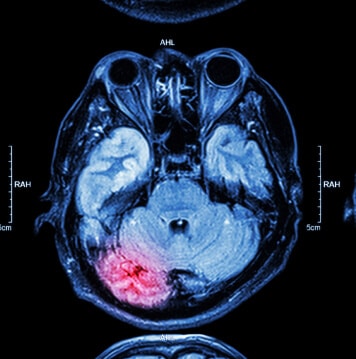

These conclusions were drawn after researchers examined the results of brain images captured by magnetic resonance imaging and diffusion tensor imaging technology.

The team also found the damage done to the brain by a TBI can be long-term, if not permanent. This was determined by images of the brain that were collected one-year after the initial patient assessment.